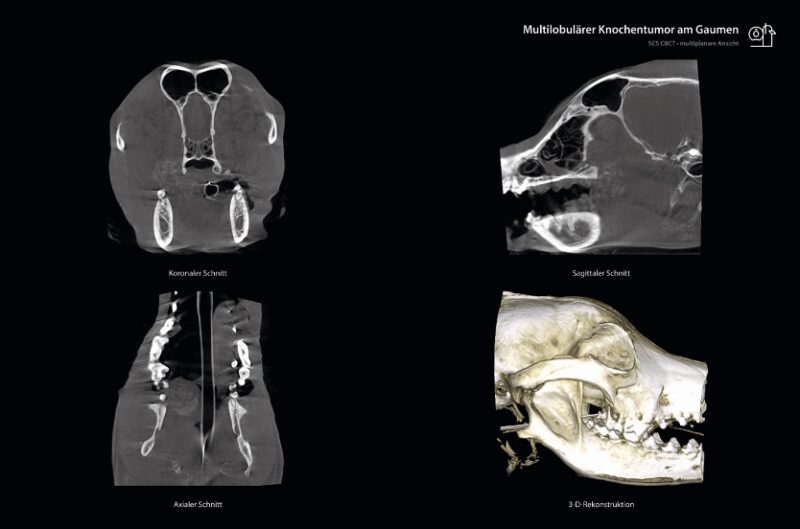

Im Vergleich zum herkömmlichen CT unterscheidet sich das SCS CBCT in mehreren wesentlichen Aspekten. Der wichtigste Unterschied liegt in der Darstellung der Ergebnisse. Dank modernster Technologien können hochqualitative und erstaunlich hochauflösende Schnittbilder erzeugt sowie eine multiplanare Darstellung der knöchernen und dentalen Strukturen (axial, sagittal, koronal sowie 3-D-Rekonstruktion gleichzeitig) erstellt werden. Die Belichtungsdauer beträgt etwa 20-30 Sekunden und bietet eine deutlich höhere Strahlenhygiene. Aufgrund einer so detailreichen Darstellung der Zahnstruktur übertrifft diese Technologie die bisher übliche dentale Röntgentechnik und hat sich in folgenden Anwendungsgebieten bereits etabliert:

Für Zahntierärzt:innen bietet die 3-D-Bildgebung von SCS – insbesondere in der Tumordiagnostik – klare Vorteile. Bisher ermöglichten 2-D-Dentalröntgenbilder eine grobe Einschätzung der betroffenen Bereiche. Durch multiplanar rekonstruierte Schnittbilder kann nun eine deutlich präzisere Abgrenzung des tumorösen Gewebes erreicht werden. Diese verbesserte Visualisierung erleichtert die genaue Planung von Operationen. Entscheidend ist, ein genaues Bild vom Ausmaß des betroffenen Gewebes zu erhalten, um präoperativ zu bestimmen, wieviel Gewebe entfernt werden muss. Eine zuverlässige Einschätzung allein durch visuelle Kontrolle ist unmöglich.

Eine präzisere Darstellung des Ausmaßes ist auch für Tierbesitzer:innen bedeutend. Viele konnten bisher aus zweidimensionalen dentalen Röntgenaufnahmen nur schwer die Ursache für das Leid des Tieres ableiten. Erst durch die Betrachtung der 3-D-Rekonstruktion ihres eigenen Hundes können sie oft das tatsächliche Ausmaß der Situation erfassen. Da die meisten Besitzer:innen den Tumor nicht sehen können, wenn das Maul geschlossen ist, besteht die Gefahr, dass die Erkrankung unterschätzt wird. Die Visualisierung über die multiplanaren CBCT-Schnittbilder ermöglicht den Besitzer:innen schnell zu erkennen, warum z.B. ein beträchtliches Stück vom Kiefer entfernt werden muss oder ob eine Operation überhaupt in Betracht kommt.